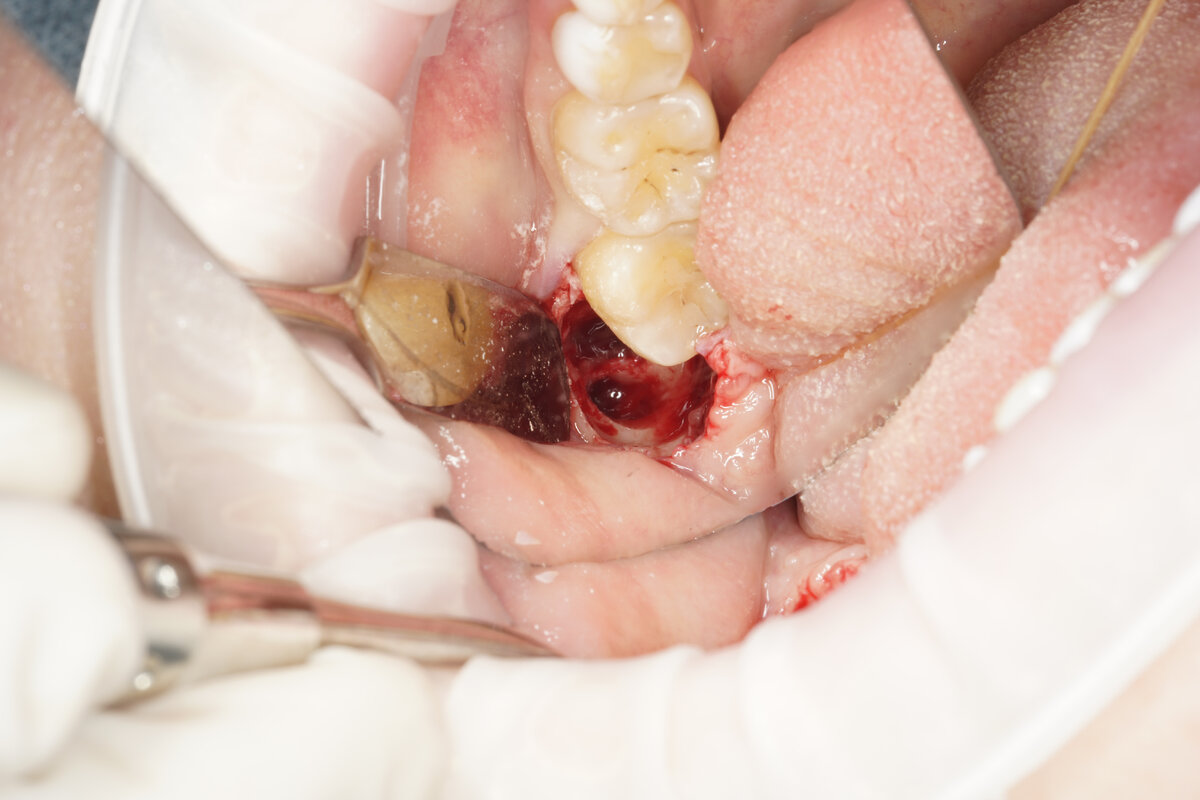

Само удаление занимает от 15 до 75 минут. Длительность процедуры зависит от анатомии зуба и его положения в челюсти. Не последнюю роль играют и мануальные навыки хирурга. Больше времени уйдет на удаление ретинированных зубов, полностью находящихся в кости. Будьте готовы, что доктор воспользуется бормашиной – с ее помощью он сможет фрагментировать зуб и удалить его атравматично, то есть с минимальным риском для окружающих тканей.

Во время удаления пациент не чувствует боли – только давление. Лёгкая чувствительность возможна при удалении зубов мудрости на нижней челюсти – в случае близкого расположения к ним нерва.

После удаления зуба в лунке формируется кровяной сгусток, а поверх ее накладываются швы. Привкус крови во рту и содержание крови в слюне не должны пугать – это норма. Насторожить должно лишь быстрое наполнение ротовой полости кровью.